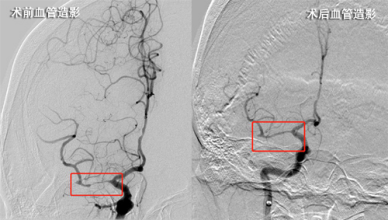

因患者错过最佳药物溶栓时间窗,与家属协商后,卒中团队立即为该患者行急诊全脑造影备支架机械取栓术。术中发现患者右侧大脑中动脉存在长节段极重度狭窄、前向血流缓慢,卒中团队讨论决定,采用血管内球囊成形术,必要时行支架植入术,尽快开通血管。经数十分钟努力,狭窄段血管开通成功,前向血流再通分级mTICI评分3级,提示血管再通成功。术中未使用支架植入,为患者省下数万元耗材费。

术后立即检查患者左侧偏瘫肢体,功能明显好转,术后几日患者肌力逐渐恢复正常,恢复生活自理能力。经过神经内科医护人员针对性诊疗和精心护理,患者的偏瘫和语言功能基本恢复正常,复查血管显示狭窄段血流通畅,现已痊愈出院。